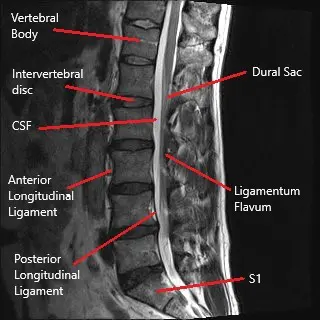

Sagittal section of the lumbar MRI.

The lumbar spine consists of five vertebrae (L1-L5) separated by intervertebral discs. These discs act as cushions to absorb shock and allow movement. The spinal cord passes through the central canal, and nerve roots branch out from the spinal cord, exiting the spinal column through the intervertebral foramen. These nerves control sensation and movement in the lower body. A herniated disc can compress these nerve roots, leading to symptoms such as pain, tingling, and weakness.

• MRI (Magnetic Resonance Imaging): The most effective tool for visualizing soft tissues like discs and nerve roots. It can confirm disc herniation and nerve compression.